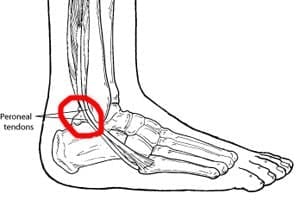

Peroneal tendon pain

What is it?

Tendons are pieces of connective tissue which join muscles to bones. The peroneals are a group of two muscles on the outside (little toe side) of the leg, and they have tendons that join them to the side of the foot.

When they are damaged, we often experience a pain that develops behind the ankle bone, or where the tendon is attached on the outside of the foot. It affects women and men equally.

What is the injury process?

It is thought the peroneal tendons become damaged by being overstretched or placed under pressure. The tendons pass around the ankle, through a lining known as the peroneal sheath.

Their function is to point the foot down and turn it way from the body .Often problems arise when they are needed to perform this function too often – such as when your foot naturally leans outwards. The tension can increase to a level that damages the tendon.